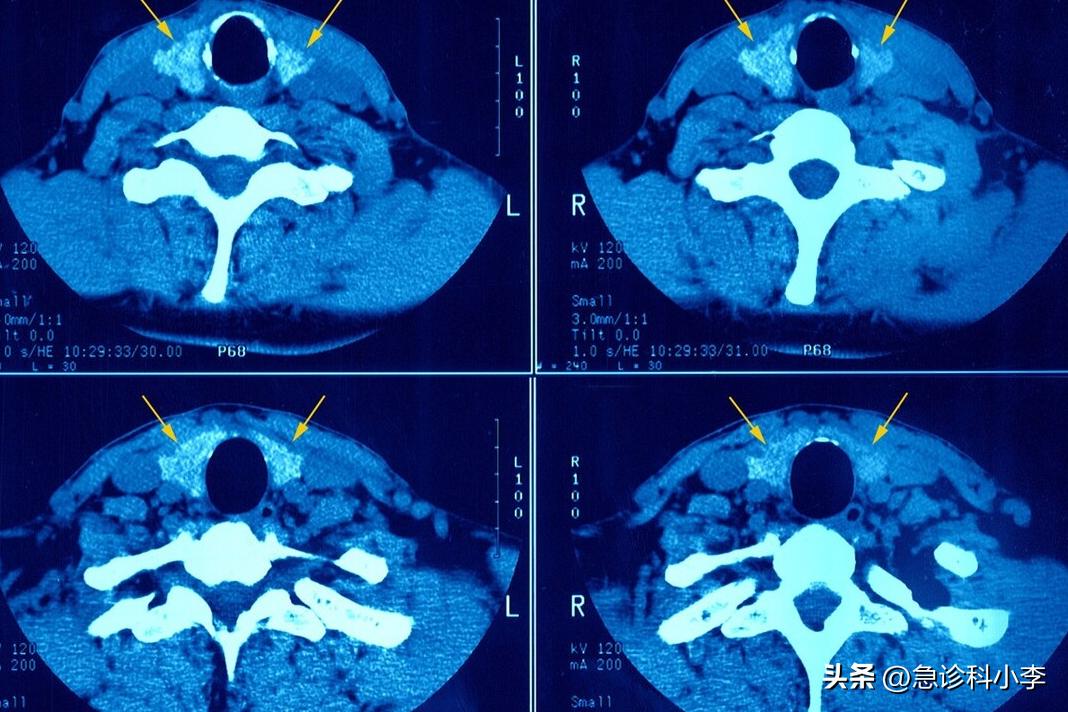

(4)颈部X线检查

一旦气管中出现浸润或者变形,则提示有恶性病变,X线也可出现 钙化表现 。所以,颈部X线还是可以用于甲状腺结节良恶性的判断的。